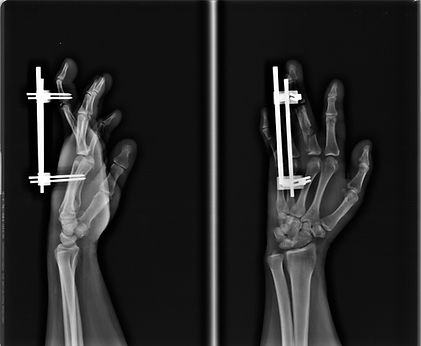

Una de las urgencias que pueden presentarse son las fracturas, estas son la ruptura total o parcial de un hueso. Puede ser producida por una caída, golpes fuertes o la contracción violenta de un músculo. Existen dos tipos: las cerradas, en las que el hueso se rompe y la piel permanece intacta, y aquellas en que la herida está abierta y el hueso fracturado se desplaza hacia el exterior.

Tienen mayor riesgo de padecer una fractura las personas con osteoporosis, aunque también llegan a ser frecuentes en niños y ancianos porque su composición ósea es más frágil.

Cada fractura necesita:

una evaluación individualizada

y un tratamiento ajustado al tipo que corresponda y a tu circunstancia personal

Puede que un tratamiento inicial pueda serte prescrito por cualquier profesional sanitario.

Pero el tratamiento definitivo y tu seguimiento te lo debe hacer un especialista en traumatología

las fracturas pueden tratarse de manera conservadora o quirúrgica.

Las operaciones de fracturas son muy variadas, tanto como los huesos y tipos que existen.

Los procedimientos pueden ir desde:

Intervenciones percutáneas, en las que apenas se hace una pequeña incisión en la piel y los cirujanos nos guiamos por las imágenes que muestra un aparato de escopia en quirófano

A operaciones donde son necesaria la reducción y colocación de distintos tipos de implantes e incluso una prótesis si se trata de una articulación.